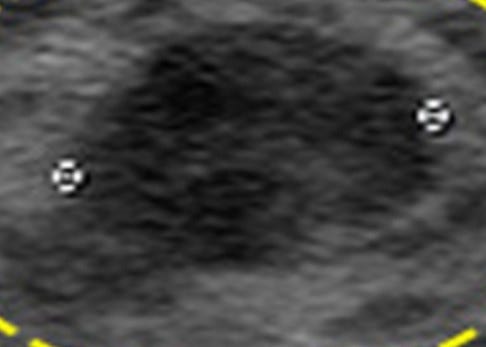

유방섬유선종 추적관찰 초음파 엑스레이검사 맘모톰예약후기 호평동 삼성베스트유외과의원

6개월마다 유방 정기점진을하기어 이번에도 예약후 호평동에 위치한 삼성베스트유의원에 방문했어요. 올해...